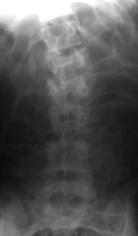

При поздних сроках от момента повреждения (более 3-4 недель) хирургическое вмешательство выполняли одномоментно из двух доступов: первым этапом из дорсального доступа устанавливали многоопорную конструкции с опорой на интактные тела позвонков в сочетании с задним локальным спондилодезом, вторым - из переднебокового доступа выполняли реконструкцию передней и средней колонн позвоночника путем дискэктомии на уровне перелома, удаления костных отломков тела позвонка и расклинивающего корпородеза аутокостью. Такая последовательность хирургического вмешательства объяснялась наличием фиброза в зоне повреждения и невозможностью осуществить адекватную репозицию только из дорсального доступа (рис. 16). Больных ставили на ноги через 10-12 дней после операции и выписывали на амбулаторное лечение в фиксирующем корсете на 16-18 день после хирургического вмешательства.

Рис. 16. Рентгенограммы пациентки М. 15 лет. Последствия взрывного перелома L1, радикулярный синдром.

А – до операции, Б – после задней непрямой репозиции, фиксации и спондилодеза в сочетании с дискэктомией и расклинивающим корпородезом аутокостью из переднебокового доступа |